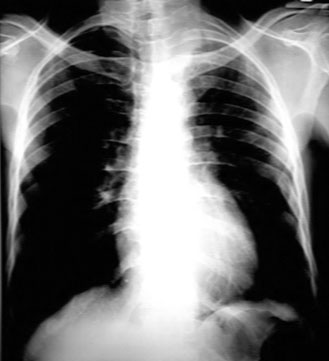

Note the apical mass.